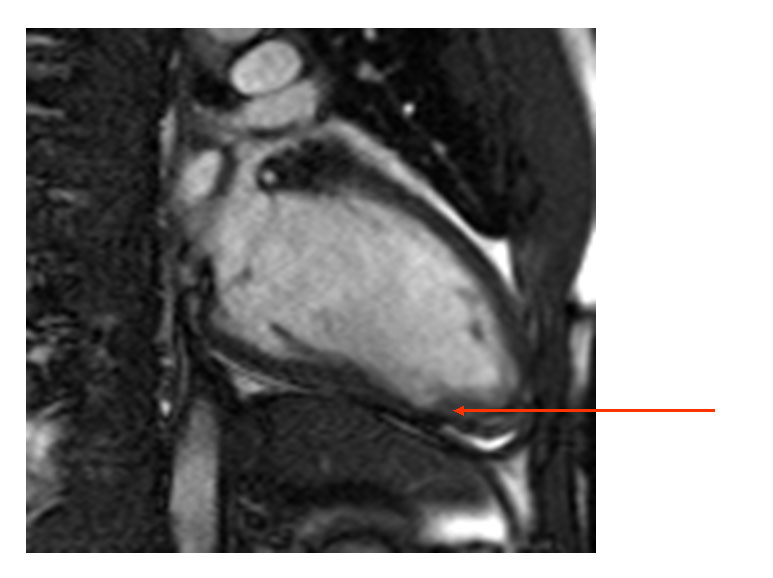

Emergency department course: The patient was initially considered low risk based on age and absence of ECG changes, and underwent acute rest myocardial perfusion imaging (MPI) for further risk stratification. This demonstrated a small sized, low-moderate grade inferior apical defect (Figure 1). Gated images demonstrated abnormal wall motion, and the study was interpreted as consistent with an acute coronary syndrome. The patient was admitted to the coronary intensive care unit. Serial markers were performed:

Subsequently, cardiac magnetic resonance imaging (MRI) was performed to determine whether there was an associated cardiomyopathy. This demonstrated a wall motion abnormality (Figure 2A) and a focal area of gadolinium uptake (Figure 2B) extending from the mid to distal inferior wall, consistent with transmural infarction, rather than myocarditis. The distribution was similar to the MPI and echocardiographic wall motion abnormalities. Given the lack of plaque on the angiogram and his young age, the presumptive diagnosis was acute thrombosis related to sickle cell crisis. Because of the delay in angiography, we have hypothesized that any visible thrombus resolved with antiplatelet and antithrombotic treatment.